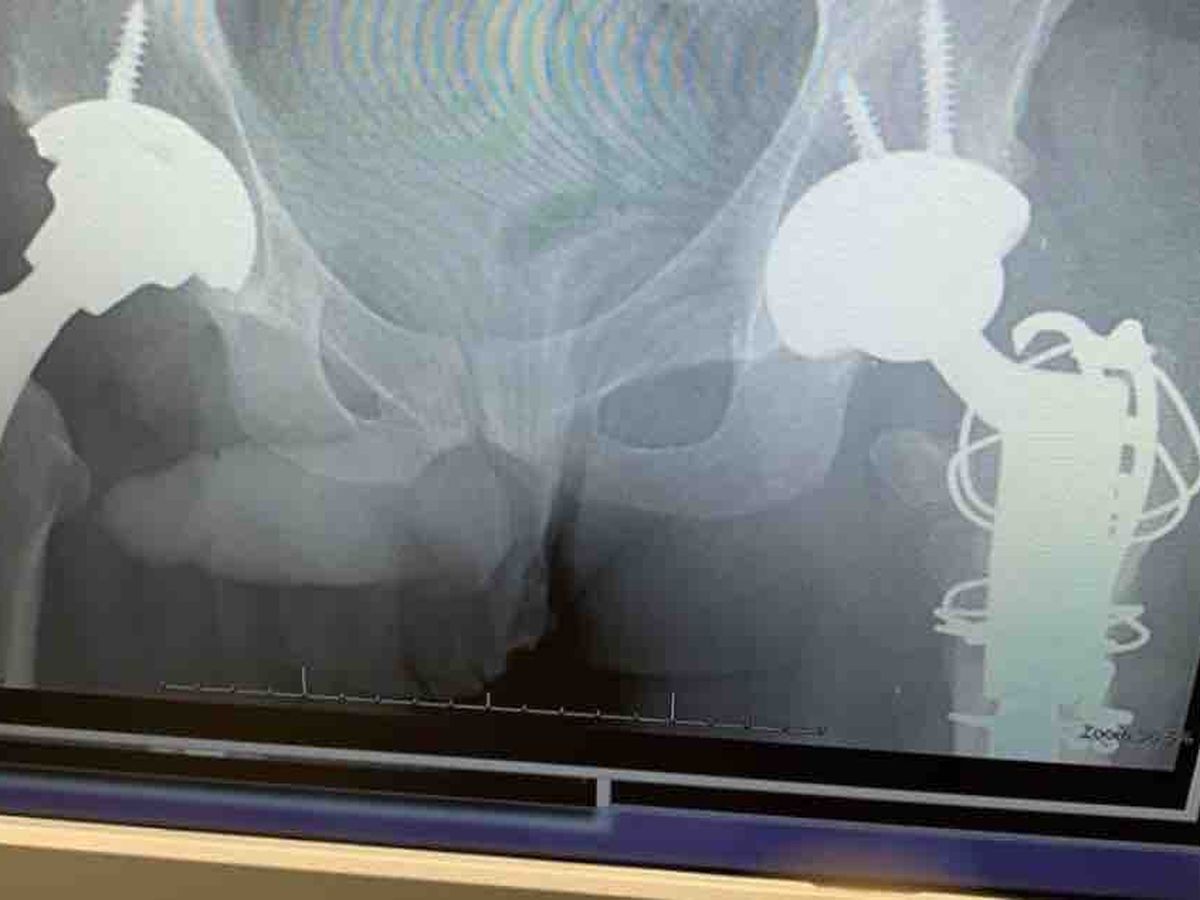

My name is Rahim Jafari. I’m a human right activist from Iran.I was tortured, there is a device in my brain. I had a brain tumor and underwent brain I was tortured by the Islamic Republic of Iran for my human and civil rights activities which resulted in multiple surgeries on my hip joint and brain in Turkey and Iran. I hello, I have an update regarding the hip replacement surgery that I was supposed to do at a private hospital in Toronto. 3 days ago, one of my friends, Dr. Mahmoudi, an orthopedic specialist, introduced me to his friend and his teacher, Dr. Olga Safir, a specialist in orthopedics and hip surgery at Mount Sinai Hospital, a public hospital. We went to the hospital after the examination and Xray,the doctor gave me an order for an urgent surgery. In this regard, I want to update the request for the campaign . The cost that is required now is due to the difficulty of the surgery and the need for at least 6 months of complete rest to recover. Considering my physical condition and the fact that both of my hip joints were operated on before, I need complete rest for recovery. Therefore, considering that I am currently living in a government-owned shelter, there is an urgent need to rent a house after the surgery, and due to the surgery, I need a 24-hour nurse and full medical care and physiotherapy, which are not covered by my insurance and I have to pay in cash. Due to the lack of money, I will continue the fund for the rent of the house and the cost of the nurse and physiotherapy. The campaign fund needs to be collected at 30 thousand dollars to cover my expenses and I am desperately asking for your help so that with your help I can recover and live a new life with less pain. Regarding the fact that this injury was done due to torture, I attached all the prison documents and arrest warrants here. Lastly, I never publicly said anywhere that I was tortured because i dont want to take advantage of my situation. Also, I am attaching all the documents of the hospital where I am going to be operated on, the documents of the previous surgeries that have been done, and all the related documents.

سلام در خصوص عمل جراحی تعویض پروتز که قرار بود بیمارستان خصوصی تورنتو انجام بدم که درخواست کمک برای هزینه عمل جراحی صندوق کمک درخواست کرده بودمکه هزینه عمل جراحی جمع و کمک بشه که بتونم عمل جراحی رو انجام بدم. ۳ روز پیش یکی از دوستای خودم جناب دکتر محمودی متخصص ارتوپد من رو به دوستش و استاد خودش دکتر Olga Safir فوق تخصص ارتوپد و جراحی hip در بیمارستان mount Sinai بیمارستان دولتی در ادرس 600 university معرفی کرد که دیروز با مترجمی یک دوست عزیز که اسمشو علنی نمیکنم رفتیم بیمارستان بعد معاینه و عکسبرداری و سفارش دکتر محمودی عزیزم دکتر دستور جراحی فوری و ارجنت رو بهمداد و قرار شد تا ماه اخیر عمل جراحی تعویض پروتز و پیوند استخون که نیاز بود رو در بیمارستان دولتی رایگان با بیمه دولت کانادا انجام بده با توجه به فوریت و ارجنت بودن دکتر safir بهم قول داد در صورت کنسلی عمل جراحی بیماری بهم زودتر از یک ماه باهام تماس میگره یا اگرم نشد تاریخ عمل جراحی ۱۵ نوامبر عمل جراحی رو انجام میده در همین خصوص من درخواست صندوق رو بخاطر رایگان شدن بیمارستان آپدیت میکنم. هزینه که الان لازم هست با توجه به سخت بودن عمل جراحی و حداقل ۶ ماه نیاز به استراحت کامل داره تا ریکاوری انجام بشه با توجه به وضعیت جسمانی من که هر ۲ مفصل hip من پروتز هستش نیاز به استراحت کامل برای ریکاوری نیاز دارم بخاطر همین با توجه اینکه الان ساکن هتلی که متعلق به دولت هستش سکونت دارم نیاز فوری و ارجنت هستش که بعد از عمل جراحی خونه ای اجاره کنم و با توجه به عمل جراحی نیاز به یک پرستار ۲۴ ساعته و رسیدگی پزشکی و فیزیوتراپی کامل دارم که هزینه های فیزیوتراپی و پرستار بیمه من کاور نمیکنه و باید نقد پرداخت کنم و با توجه به نداشتن پول ادامه صندوق رو برای اجاره خونه و هزینه پرستار و فیزیوتراپی ادامه میدهم که صندوق کمک هزینه ۳۰ هزار دلار نیاز هست جمع بشه… و از تک تک شما درخواست کمک عاجزانه دارم که با کمک هاتون بتونم ریکاوری و زندگی جدید بدون درد شروع کنم… با توجه به اینکه حقوق دیسبلیتی من در انتاریو بنابدلایل ( محرمانه ) فعلا تعلیق شده که مدارکش رو پیوست میکنم که تایید بشه تعلیق حقوق. در خصوص اینکه این اسیب که بخاطر شکنجه در جریان بازداشت من انجام شده که بسیاری از دوستان بهم پیام دادن که این مشگل بخاطر تصادف هستش و من دروغ چندین ساله میگم شکنجه بوده… در این خصوص تمام مدارک زندان و حکم های بازداشت احضاریه رو در اینجا پیوست میکنم که تایید به درگیری شکنجه من هستش… و در آخر دوستایی که تاکید میکن برای تصادف هستش این آسیب تقاضا دارم فقط مدرکی به عنوان مسند ارائه بدن که این آسیب بخاطر تصادف بوده و من همینجا قول میدم اگه فقط یک مدرک ارائه بدن و ثابت کنن برای تصادف بوده تمام پول که قرراره صندوق جمع بشه رو به عنوان پاداش به اون فرد که مدرک علنی کرده می دهم… و در اخر من هیچوقت بصورت علنی هیچوقت هیچ کجا نگفتم شکنجه شدم چون قصد سواستفاده نداشتم و فقط سازمان ملل خبر داشت که بخاطر همین من مدارکی ارائه کردم بهم تمام امکانات و کمک های غیرقابل جبران بهم کردن و به من شهروندی کانادا ارائه دادن… اگه یکدرصد مدارک های من دروغ و جعلی هیچوقت سازمان ملل به درخواست کمک من جواب رد میداد . در آخر تمام مدارک بیمارستان که قرار عمل جراحی بشم و مدارک جراحی های قبل که انجام شده و تمام مدارک عکس ها رو پیوست میکنم که تایید کنه تمام حرف هام رو…